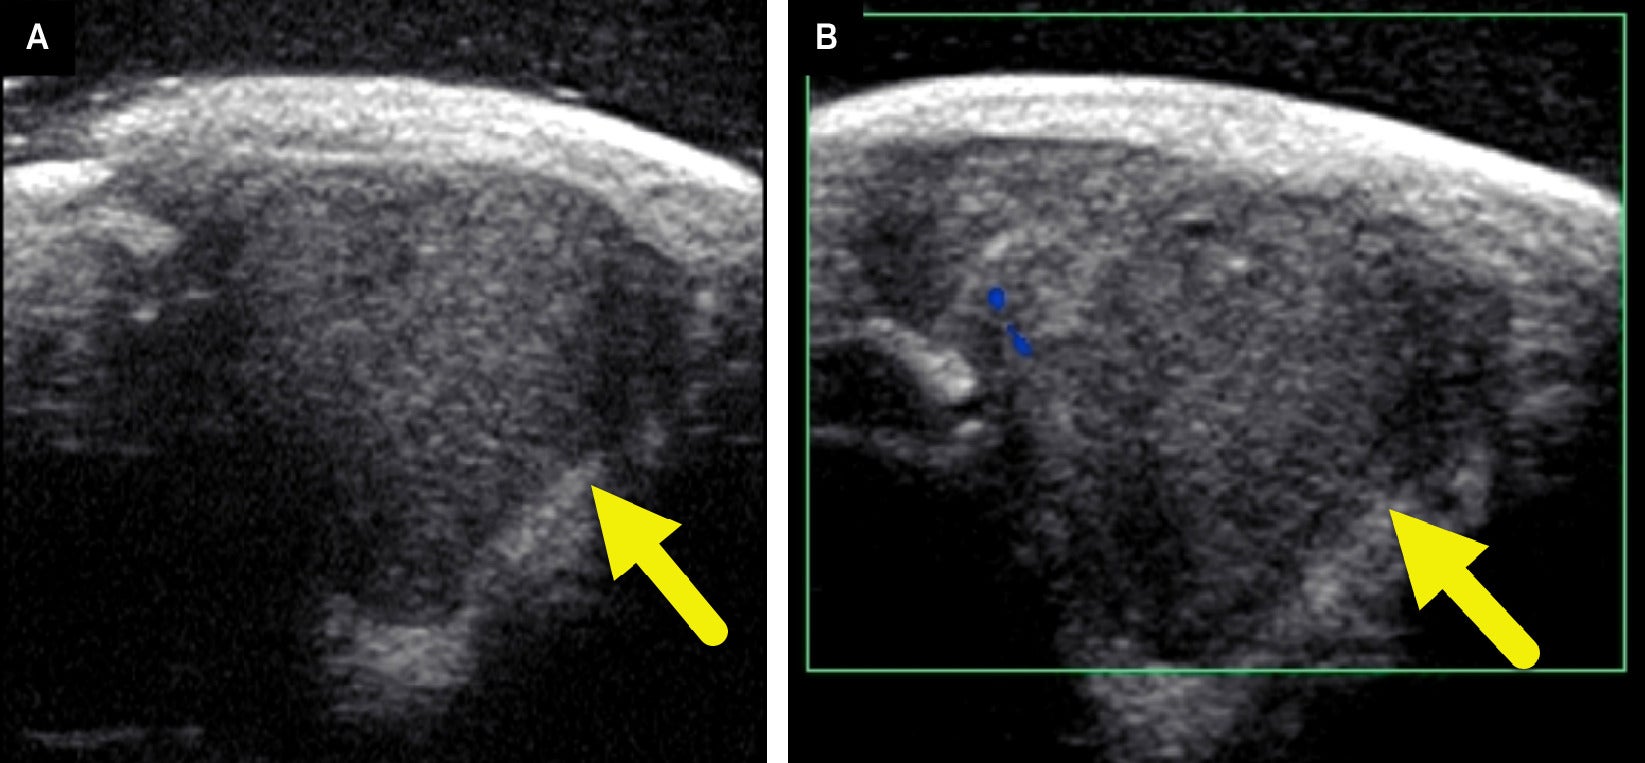

A radiograph of the left hand ( Figure 1 ) revealed a soft tissue mass in the web space between the ring and small fingers. No osseous abnormalities were noted. Ultrasound (US) ( Figure 2 ) demonstrated a well-circumscribed, hypoechoic soft tissue mass measuring 1.4×1.3×1.6 cm. No internal vascularity was noted.

(A) US of the soft tissue mass shows a solid hypoechoic lesion (arrow) at the area of concern. There is a small amount of echogenic fat along the lateral and deep margins of the tumor. (B) Color Doppler US shows minimal internal Doppler flow.

Radiographically, LGFMS appears as a noncalcified soft-tissue mass without adjacent bone erosion or destruction ( Figure 1 ).4 It is a solid hypoechoic mass on US with a more hypoechoic rim.4 It may have regions of nodularity and minimal internal blood flow on color Doppler ( Figure 2 ).4 The tumor is heterogeneous on CT, with heterogeneous enhancement and hypodense relative to muscle.4, 5 On MRI, the mass is hypo- to isointense compared with muscle on T1-weighted images and heterogeneous on T2-weighted images.5 It enhances heterogeneously after the administration of contrast media. Peritumoral edema is common.5 When an LGFMS is located within an intramuscular compartment, the “split fat” sign may be present.5 This finding is present when a rim of fat surrounds the tumor. The tumor may also have a gyriform pattern on T2-weighted or post-contrast sequences.4